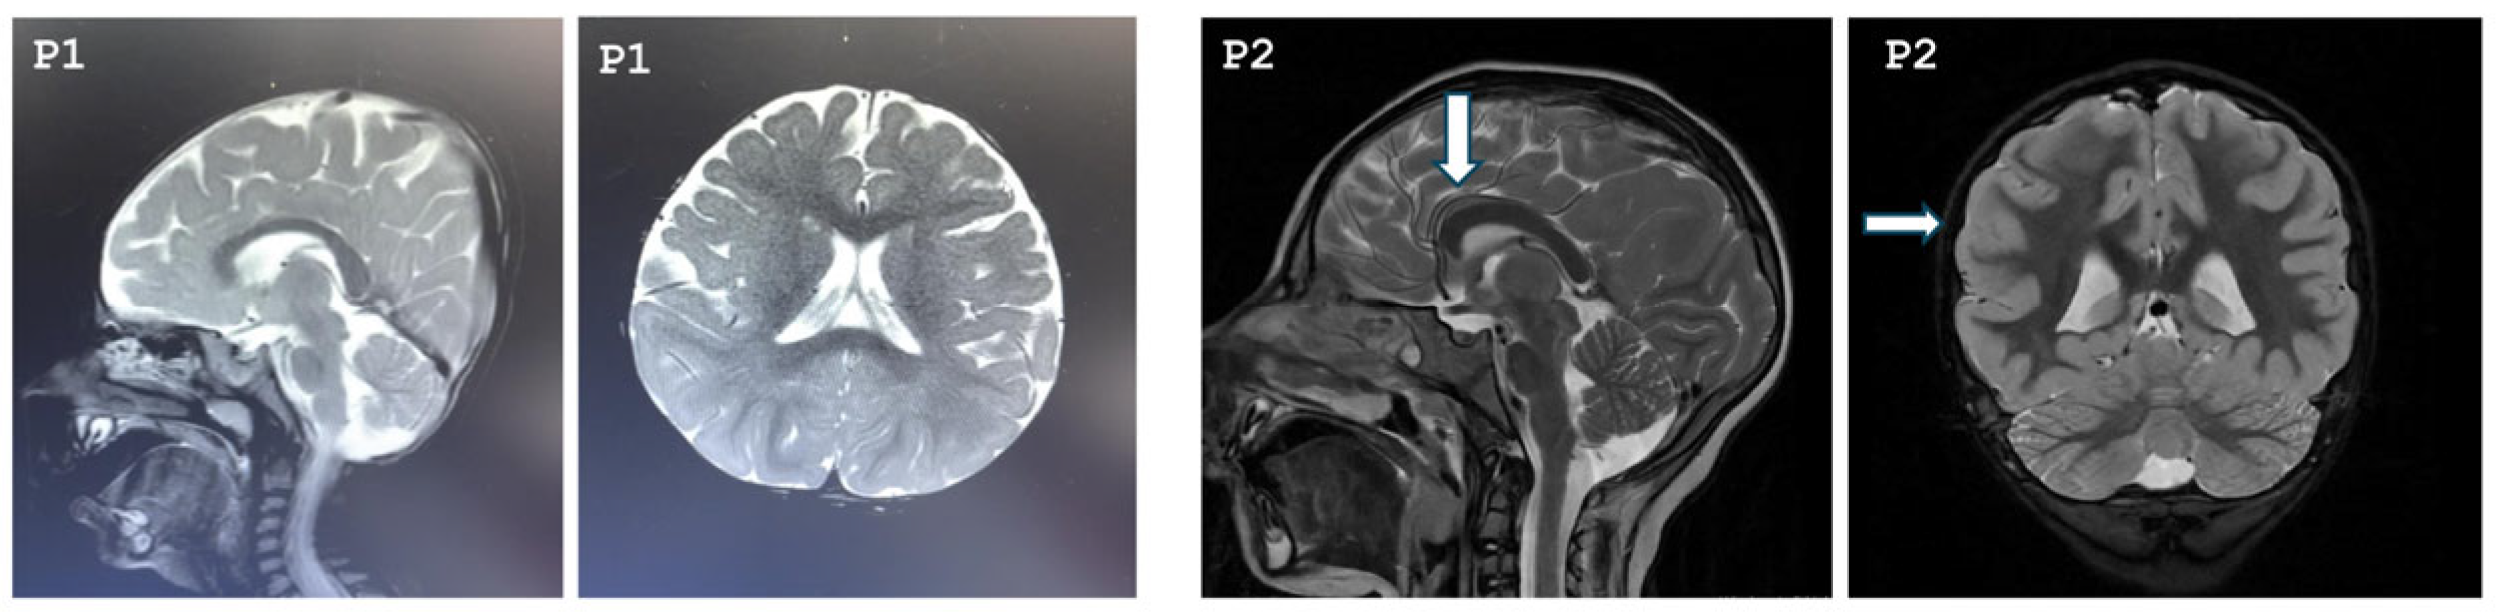

Our study included seven patients diagnosed with MCPH3 from six different families. Three patients were females, and four were males. All patients were born to consanguineous parents who were first-degree cousins. The mean age of the patients was 7 years 3 months. Two of the patients were born late preterm, and all patients had birth weight and length appropriate for their gestational age. Compared to their motor skills, their speech development was more delayed. Two of the patients exhibited neuromotor developmental delay, and speech delay was noted in six patients. Five of the patients had learning difficulties and were receiving special education; evaluation was inconclusive for one patient (Patient 1) due to their young age. One patient had a history of seizures. On physical examination, all patients were found to have severe microcephaly, with a mean head circumference of −6.1 SDs (range: −7.9 to −3.7 SDs). Three of the patients (Patients 1, 3, 5, 7) exhibited postnatal short stature, while two patients had growth deficiency in weight (Patients 1, 6). On dysmorphic examination, the most prominent features observed in the patients were brachycephaly, hypertelorism, epicanthus, high-arched eyebrows, high nasal bridge, and micrognathia. Other dysmorphic findings were not distinctive and appeared to be patient-specific, such as sloping forehead, synophrys, upslanting palpebral fissures, ptosis, anteverted nares, low columella, long philtrum, and thick vermilion border. Conical teeth were observed in Patients 4 and 5. Additionally, the exfoliation of primary teeth had not yet occurred in Patient 5. Cutaneous pigmentary abnormalities of varying sizes in different body regions were observed in six of the seven patients. Cranial magnetic resonance imaging (MRI) revealed diffuse parenchymal volume loss in both cerebral hemispheres in Patient 1. In Patient 2, the frontal lobes appeared smaller than normal in both hemispheres, with associated findings of hypoplastic corpus callosum, pachygyria, and absence of the pineal gland. In Patient 6, an arachnoid cyst measuring 14 mm was detected in the retrocerebellar region. MRI findings were normal in the remaining patients. The cranial MRIs of Patients 1 and 2 are shown in Figure 1.

Figure 1. Cranial MRI images of Patient 1 and Patient 2. P1: T2-weighted sagittal and axial cranial MRI of Patient 1 demonstrating bilateral diffuse cerebral atrophy. P2: The arrows indicate a hypoplastic corpus callosum and pachygyria, respectively, in Patient 2.

The vast majority of patients with MCPH3 do not exhibit distinctive dysmorphic facial features. In a subset of patients, the most notable findings include a sloping forehead, hypertelorism, epicanthus, and a high nasal bridge [10,11,13,24]. In our patients, hypertelorism, epicanthus, and a high nasal bridge were the most prominent facial features, with the additional observation of high-arched eyebrows, a finding not previously reported in the literature. Nevertheless, as noted above, distinguishing patients based on phenotype alone is rarely possible. In most patients with MCPH3, neuromotor development, including head control, independent sitting, and walking, is appropriate for age; however, mild delays have been observed in some individuals [25,26]. Mild delays in neuromotor development were present in two of our patients (P1 and P3). In nearly all patients with MCPH3, mild to moderate intellectual disability is present, while severe impairment is observed in only a small number of cases [10,26,27]. In our cohort, one patient could not be reliably assessed due to young age, while another 4-year-old patient (P4) had no intellectual disability and had never received special education; however, no formal testing had been performed. In contrast, his older sister, carrying the same mutation, had intellectual disability and was receiving special education. Cranial MRI findings in MCPH3 patients include reduced brain volume, gyral simplification, agenesis, hypoplasia, or dysgenesis of the corpus callosum, and enlargement of the cisterna magna. In the study by Erdogan et al. (2025) [10], previously unreported findings such as an arachnoid cyst and colpocephaly were documented. Nasser et al. (2020) [26] identified inter-hypothalamic adhesion (IHA) in 5 of 7 patients; however, none of their patients exhibited signs suggestive of hypothalamic dysfunction, such as micropenis, diabetes insipidus, or hypertension. IHA has not been reported in any MCPH3 patient prior to these observations. Nevertheless, when particularly thin or small, IHA may not always be detectable on routine brain MRI. Therefore, high-resolution imaging protocols with thin slices should be employed. All of our patients underwent cranial MRI, with pathological findings detected in only three patients. In Patient 1, diffuse parenchymal volume loss was observed in both cerebral hemispheres, whereas Patient 2 presented with reduced frontal lobe volumes, hypoplastic corpus callosum, pachygyria, and absence of the pineal gland. To the best of our knowledge, pachygyria and absence of the pineal gland have not been previously reported in other MCPH3 patients. In Patient 6, a retrocerebellar cyst measuring 14 mm was detected, similar to the finding reported by Erdogan et al. (2025) [10]. These findings all suggest that cranial involvement in MCPH3 is likely heterogeneous. To the best of our knowledge, seizures have been reported in 26% of patients with MCPH3 in the literature, including generalized tonic–clonic seizures and infantile spasms [10,11,12,13,14,18,23,24,25,27,28,29,30,31,32]. Consistent with the literature, one of our patients had generalized tonic–clonic seizures that began at the age of four. Only a small number of MCPH3 patients in the literature have undergone cranial MRI. Therefore, we could not obtain sufficient information to determine whether there is an association between seizures and cranial involvement. However, in the literature, patients with seizures who underwent cranial MRI were found to have non-specific findings—such as enhancement in the white matter, dilated ventricular system, thinning of the corpus callosum, and cerebral volume loss—which were also observed in patients without seizures [14]. Ataxia has been reported in only a few patients to date in the literature [13,26]. In the study by Jouan et al. (2016) [33], ataxia was observed in three patients with biallelic CDK5RAP2 mutations who presented with mild learning disability and agenesis of the corpus callosum, but without microcephaly. In our patient cohort, ataxia was identified in two individuals. As the mutations in our patients were novel, comparison with previously reported cases in the literature was not possible.